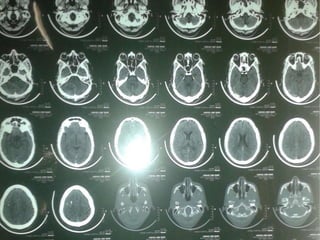

CT-BRAIN REPORT

 CT BRAIN AXIAL SECTIONS SHOWING

1. HYPERDENSITY IN THE RIGHT FRONTAL

REGION

2. HYPERDENSITY IN THE R TRANSVERSE

SINUS

3. HYPODENSITY IN THE SUPERIOR SAGITTAL

SINUS (?EMPTY DELTA SIGN)

 SUGGESTIVE OF ?PARENCHYMAL

HEMORRHAGE WITH CORTICAL VEIN

THROMBOSIS ?CALCIFIED GRANULOMA.